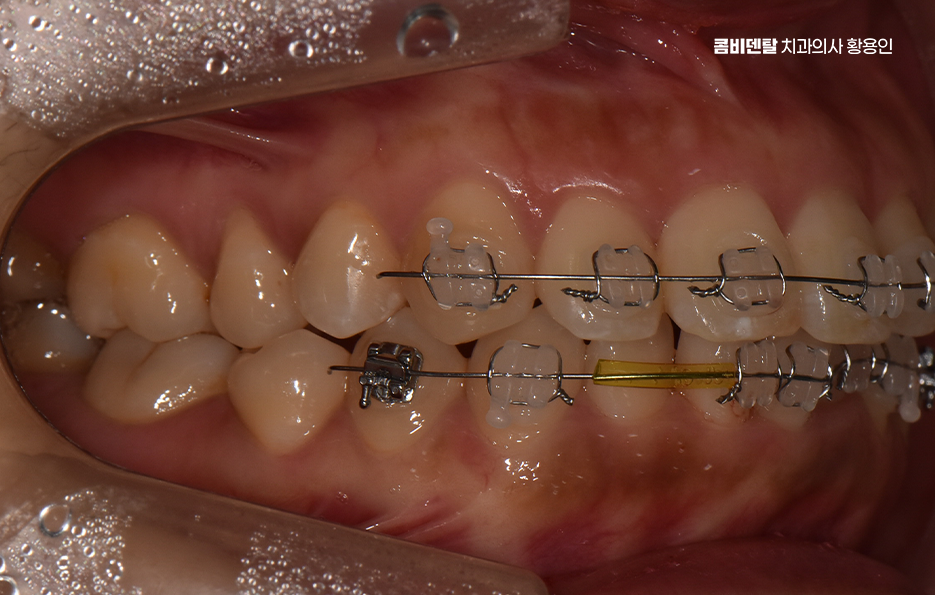

앞니 부분 교정이라는 건 말 그대로 전체 치아를 전반적으로 움직이는 게 아니라, 웃을 때 보이는 앞니 위주로 배열이나 틀어짐, 벌어짐 등을 정리하는 방식으로 앞니 부분 교정은 치료 시간과 비용, 교정 장치에 대한 부담을 줄일 수 있어서 치료가 가능한 케이스에 해당된다면 앞니를 전체교정에 비해 빠르게 개선할 수 있어요

앞니 부분 교정은 단순히 환자분이 원한다고 선택 가능한 것은 아니며 앞니만 따로 움직일 수 있을 만큼 주변 치아나 교합 상태가 안정적인 경우여야만 적용이 가능한 거예요.

그래서 단순히 앞니 사이가 벌어졌거나, 살짝 돌아가 있거나, 비대칭으로 삐뚤어진 경우처럼 부분적인 배열 문제일 때, 즉 전체적인 교합이나 턱의 위치에는 큰 문제가 없고 미세한 심미적인 조정이 필요한 경우에만 앞니 부분 교정이 효과적으로 작용한다고 볼 수 있어요

특히 성인 교정 환자분들 중엔 전체 교정을 하기엔 부담스럽고, 앞니만 조금 고치고 싶은 분들도 많아서, 이런 경우에는 부분 교정이 현실적이고 빠르게 결과를 낼 수 있는 치료 방식이 되는 거예요.

앞니 부분 교정이 가능한 대표적인 케이스로는 먼저 앞니 사이가 벌어진 ‘정중 이개’ 상태로 앞니 두 개 사이에 공간이 벌어져서 웃을 때 눈에 띄는 경우인데 이건 미세하게 치아를 당겨주거나 배열을 조정하는 것으로도 정리될 수 있어요.

또 하나는 앞니 한두 개가 뒤로 들어가 있거나, 다른 치아에 비해 튀어나온 경우로 이런 경우는 전체 교합에는 영향이 없지만 앞니 라인 자체가 삐뚤하게 보여서, 미소선이 비대칭으로 보이고 인상이 흐려지는 경우가 많은데 이런 경우도 앞니만 살짝 앞으로 빼주거나, 뒤로 넣어주는 방식으로 라인을 정리하면 인상이 부드러워 보이게 할 수 있어요.

앞니 부분 교정 가능한 다음 사례로는 치아가 겹쳐져 있는 경미한 부분 교차 교합인데 특히 아래 앞니 두세 개가 겹쳐 보이거나, 웃을 때 위 앞니 끝이 들쑥날쑥해 보일 때도 앞니 부분 교정으로 배열을 맞출 수 있으며 이런 경우는 부분 교정 만이 아니라 투명교정으로도 가능한 경우도 있어요

그런데 앞니만 건드리는 교정이라 하더라도 치아는 전체적으로 연결돼 있기 때문에, 단순히 눈에 보이는 앞니만 보고 ‘이건 부분 교정으로 되겠지’라고 판단하면 오히려 문제가 생길 수 있어서 앞니 부분 교정도 사전에 정밀한 진단이 필수이고 전체적인 교합 상태, 위아래 치열의 중심선이 맞는지, 앞니의 돌출 각도나 회전 상태, 잇몸뼈의 두께나 여유 공간 등을 모두 고려해서 가능 여부를 판단해야 하는 거예요

부분교정이 가능하다고 결론이 나면, 그때부터 어떤 방식으로, 얼마나 오랜 시간 동안 치료할 수 있을지 구체적인 계획을 세우게 되는 것이고 여기서 중요한 건, 부분 교정이라고 해서 모든 케이스가 간단하게 끝나는 건 아닌데 보통 3개월에서 6개월 정도면 끝난다고 하지만, 케이스에 따라 8개월 이상 걸리는 경우도 있고 유지 장치 착용도 고려하면 그저 단기 치료로만 끝나는 것은 아니기 때문에 치료 전에 교정 전문의와 충분히 먼저 상의가 필요한 거예요